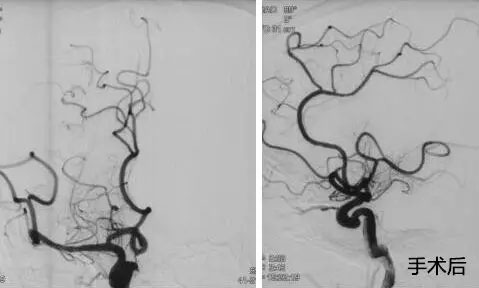

▲ 患者取栓前后DSA造影圖

10:00am,患者被送入手術(shù)室,全麻下行全腦血管造影示:右側(cè)頸內(nèi)動脈處血流完全閉塞,血栓位于右側(cè)頸內(nèi)動脈T型分叉部,其他血管代償不好,必須及時取栓干預。將微導管、微導絲送達血栓遠瑞,微導管、微導絲到位后,成功釋放支架,多次抽吸+支架拉栓,歷時三個小時,取出大量血栓,患者血管達到2B級開通,血管恢復了供血。術(shù)后,轉(zhuǎn)入九樓ICU。目前患者狀態(tài)平穩(wěn),正在康復中。